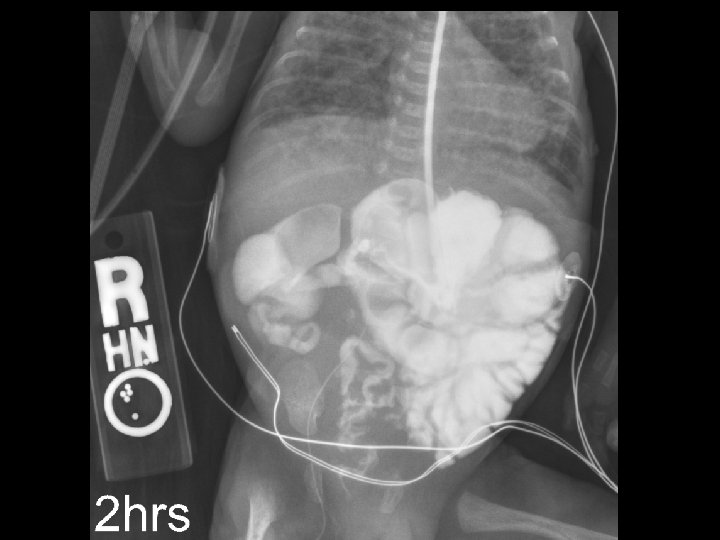

Case 2 Radiology Evaluation • Upper GI – Flow through normal duodenum, duodenal-jejunal junction, jejunum • Contrast enema – Microcolon – Distended RUQ loops do not fill during enema • Small bowel follow-through – Opacification of distended loops Jose Chavez CHO MR 960117

Case 2 Radiology Diagnosis • Microcolon • Dilated ileum secondary to obstruction • Differential diagnosis: – Stricture – Adhesions – Meconium Ileus Jose Chavez CHO MR 960117

Case 2 Surgery • Exploratory laparotomy • Extensive lysis of adhesions • Resection of 11 cm of distal ileum secondary to a concealed perforation • Creation of a double-barrel ileostomy Jose Chavez CHO MR 960117

Case 2 Findings at Surgery “Most of the small bowel in the proximal part of the jejunum all the way to the distal jejunum was quite small, and so was the ascending, descending colon. The distal small bowel appeared very distended and there was a lot of adhesions in the right lower quadrant involving several loops of distal ileum. It was apparent that there was a concealed perforation involving a segment of the distal ileum causing a significant amount of inflammatory changes and adhesions, which is causing the bowel obstruction. ” Jose Chavez CHO MR 960117